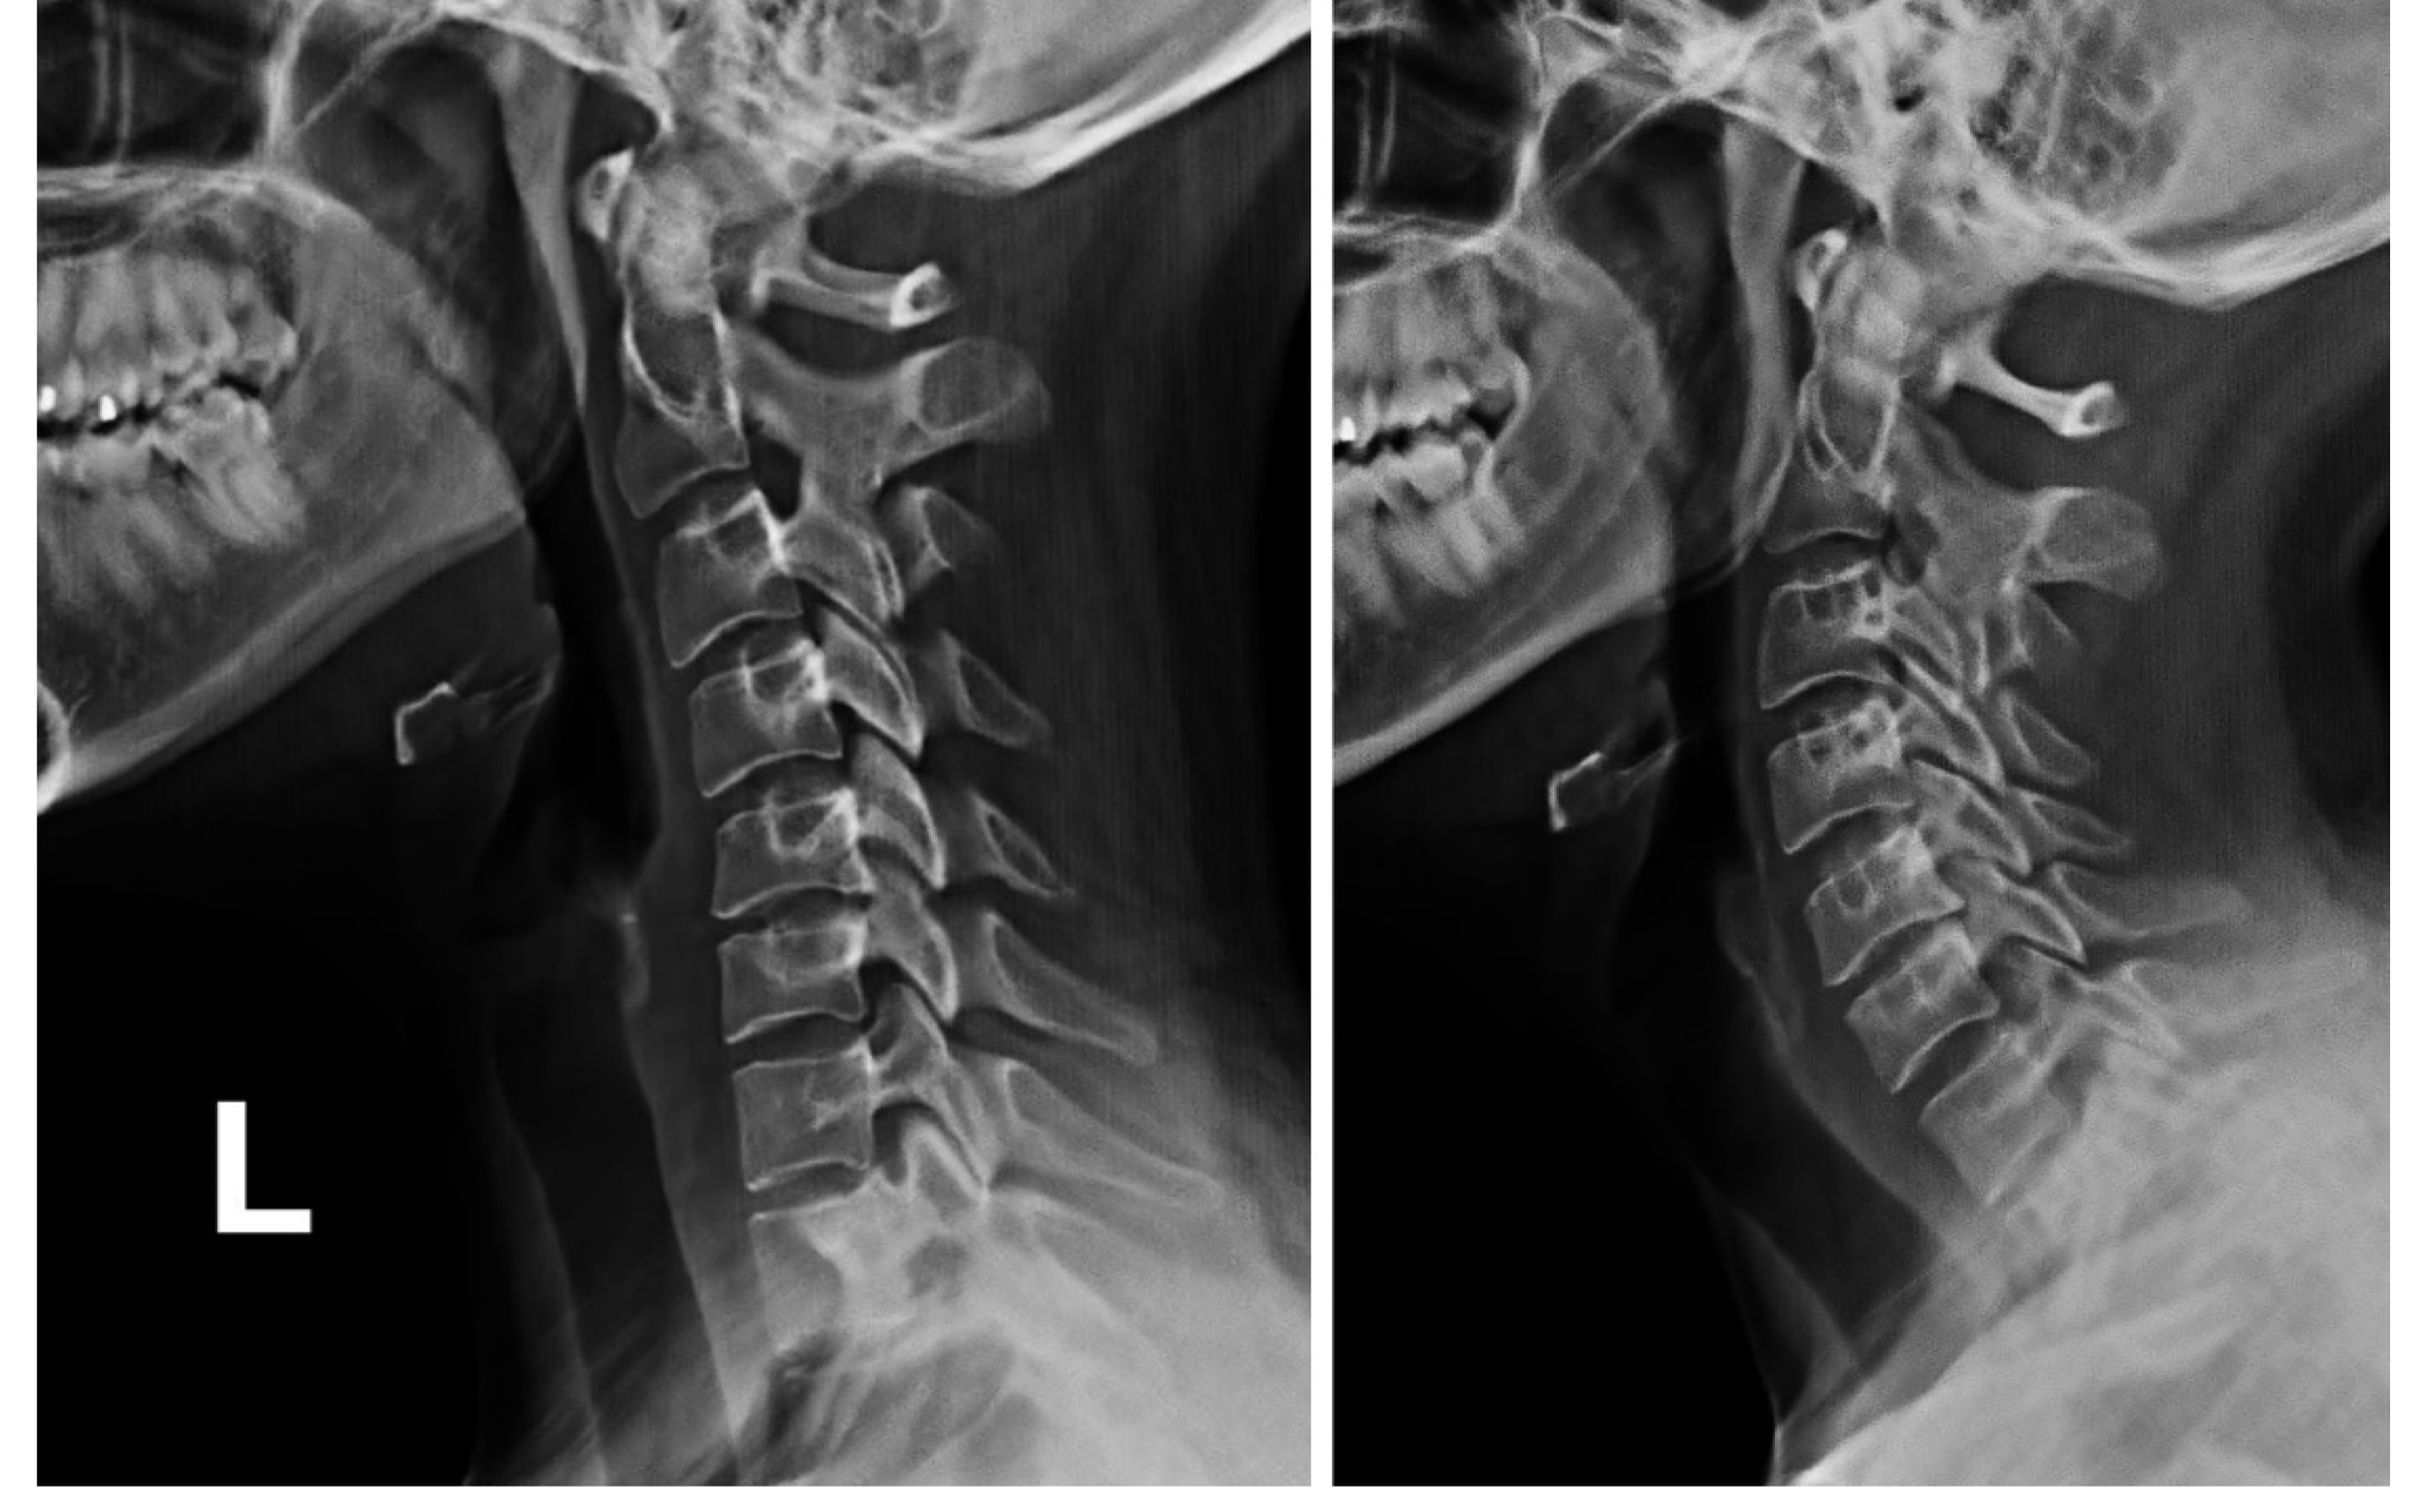

With forward head posture the cervical vertebrae are displaced anteriorly and this decreases the spaces between each joint on the posterior side (this is shown on the picture below on the right).  Since there are nerves that come out from the posterolateral area between each vertebrae, there is an increased likelihood of the nerves being affected as well as degeneration in the lower cervical spine over time.  With an upright neck, as shown in the picture below on the left, there are equal spaces between each vertebrae (4).  Common muscles that get tight with a forward head posture are the levator scapulae, semispinalis capitis, anterior scalenes, suboccipitals, and sternocleidomastoid muscles (3).

Cervical spine on one side shows equal spaces between vertebrae while a forward head posture has a decrease in these spaces.

LEFT: shows an upright neck with equal spaces between vertebrae. RIGHT: forward head causes decrease in the spaces on the posterior side of the vertebrae